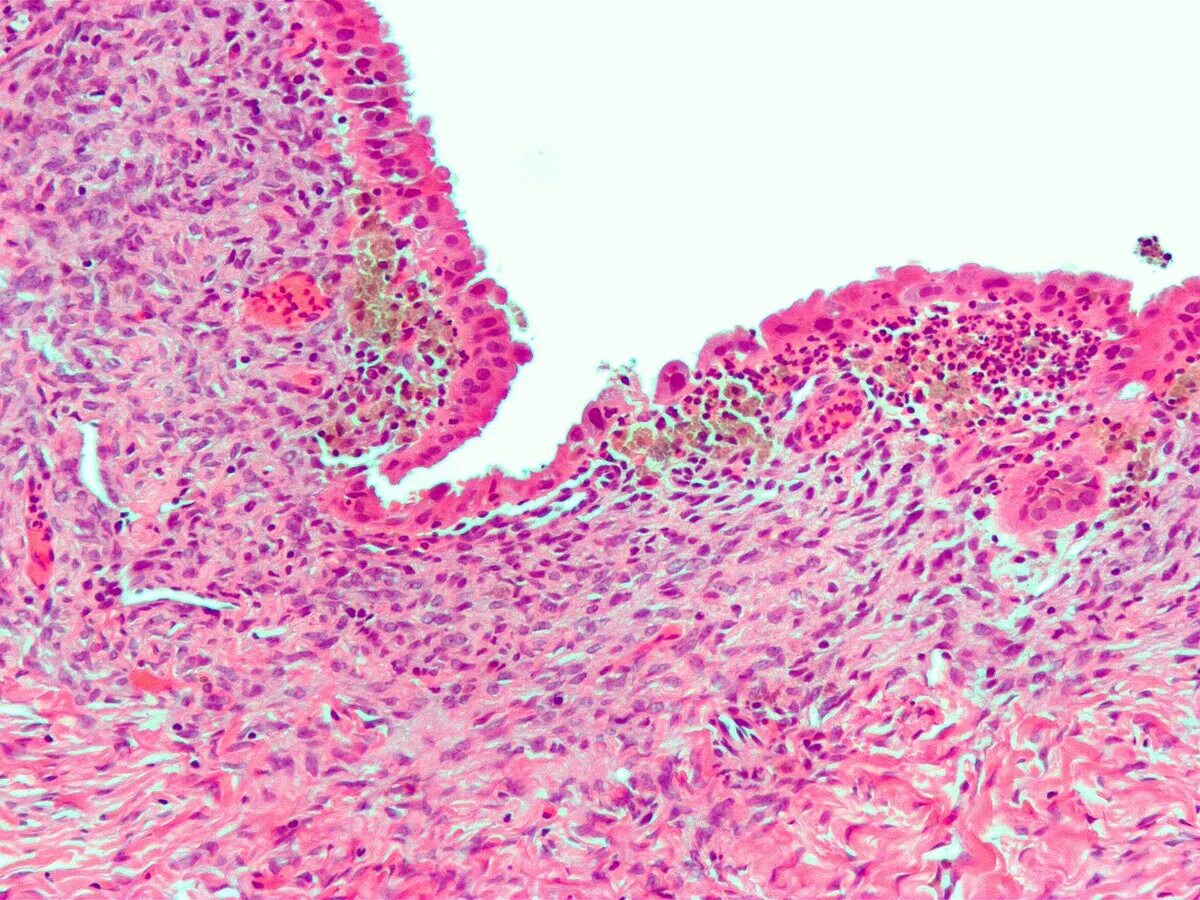

Эндометрит гистология